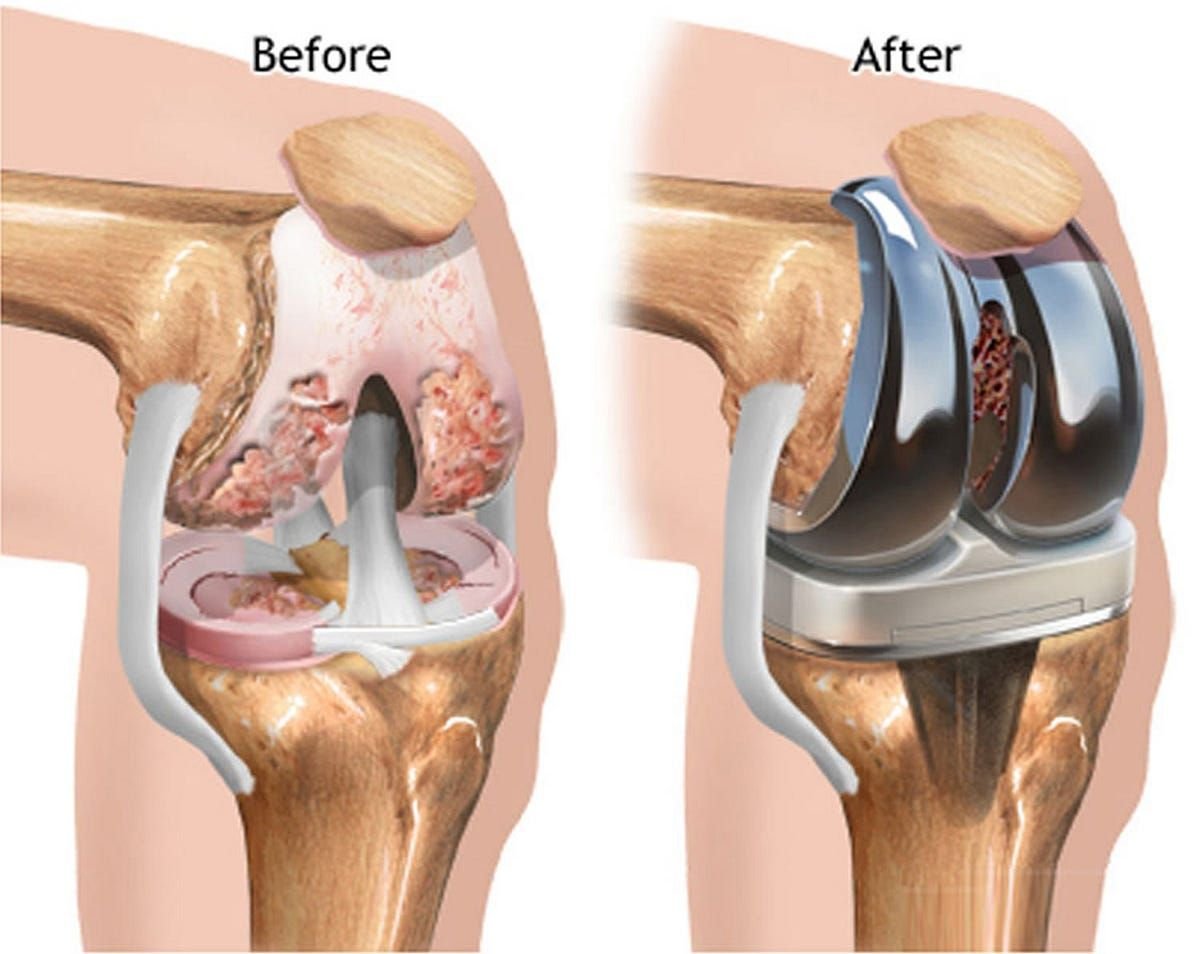

Joint replacement surgery reduces pain, enhances mobility, and restores active, healthy daily living.